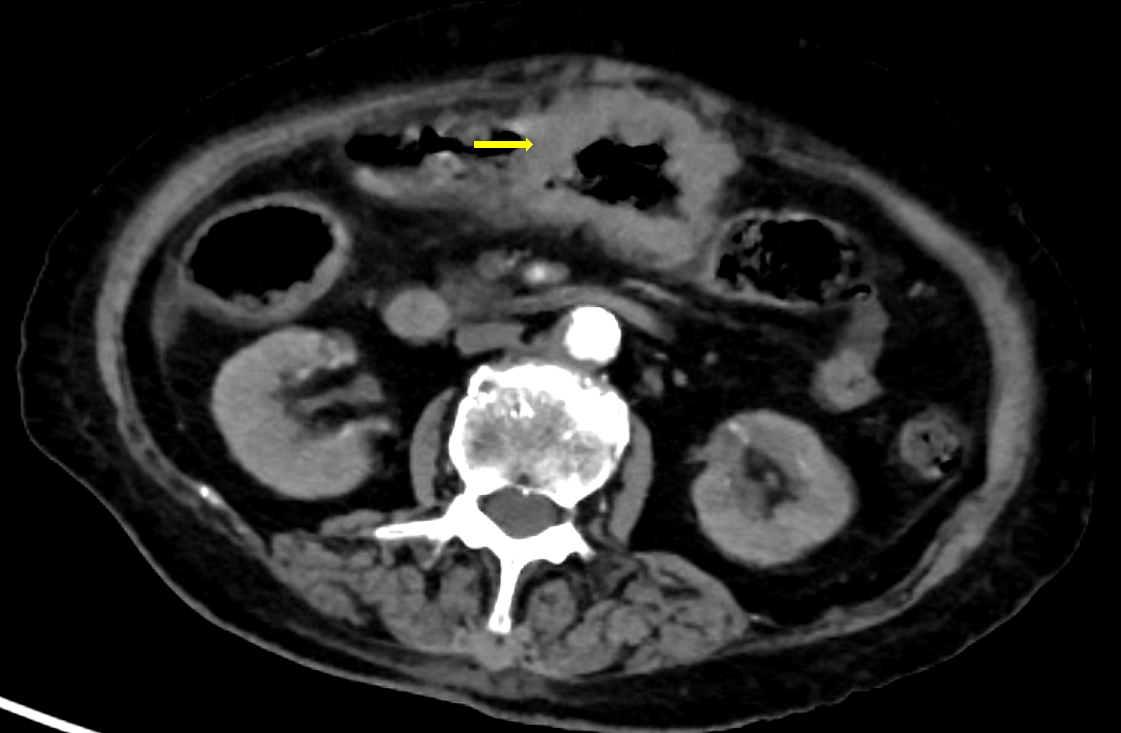

术前的腹部增强 CT 提示,王奶奶横结肠中段有节段性肠壁增厚,累及长度约为 58 mm,最厚处约 16 mm,局部管腔狭窄并伴有周围淋巴结转移。这意味着肿瘤已大幅挤占肠道,如不及时切除,可能完全堵塞肠管甚至出现肠管穿孔危及生命。